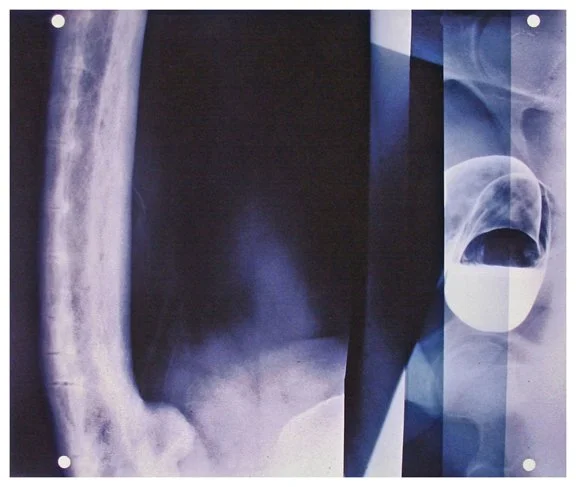

Insight is a series of collaged X-ray fragments, which were digitally composed into giclée prints. They speak not only of the body’s interior, but of the human experience it contains.

Drawn from DNA sequencing gels, mammograms, ultrasound scans, and cell cultures grown in Petri dishes, these compositions reframe diagnostic materials as metaphoric landscapes. What once served to identify illness becomes a language of line, texture, and light. They serve as a quiet meditation on fragility, resilience, and the unseen forces that shape us.

Each image in Insight is both an anatomical artifact and an artistic inquiry. Each one is part of my ongoing exploration of the relationship between Art, Science, and Medicine. Through digital layering and compositional play, I aim to dissolve the boundary between clinical detachment and emotional intimacy by inviting viewers to look inward and find meaning in the microscopic.